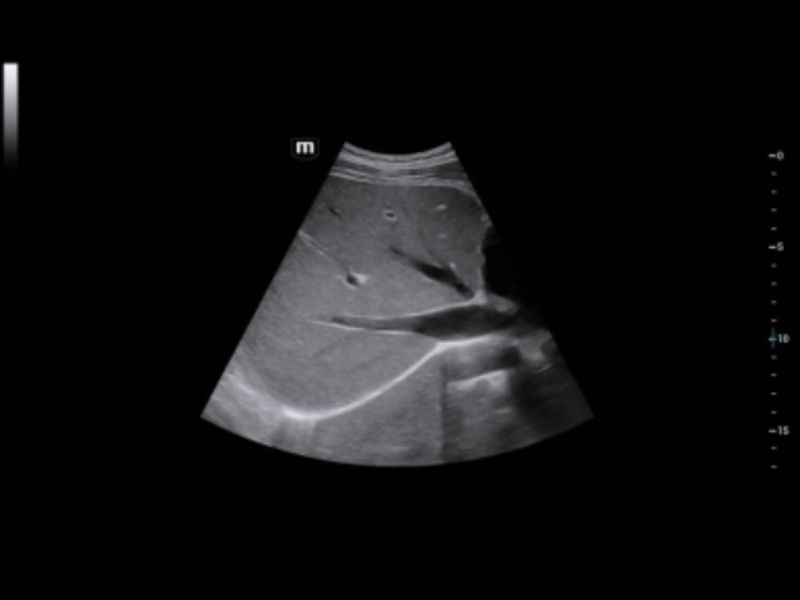

A plataforma ZST + é uma inovação extraordinária, representando uma evolução do ultrassom. Transformando métricas de ultrassom de formação de feixe convencional para processamento baseado em dados de canal. Ela supera a limitação tradicional de trade-off entre resolução espacial, resolução temporal e uniformidade de tecido, fornecendo qualidade de imagem excepcional para soluções de imagem infinitas com melhorias ininterruptas.

Solução de imagem geral

HRI inteligente

Reconhecimento automático do córtex hepático e renal e cálculo da taxa de brilho

iToque⁺

Otimização de imagem dinâmica em tempo real